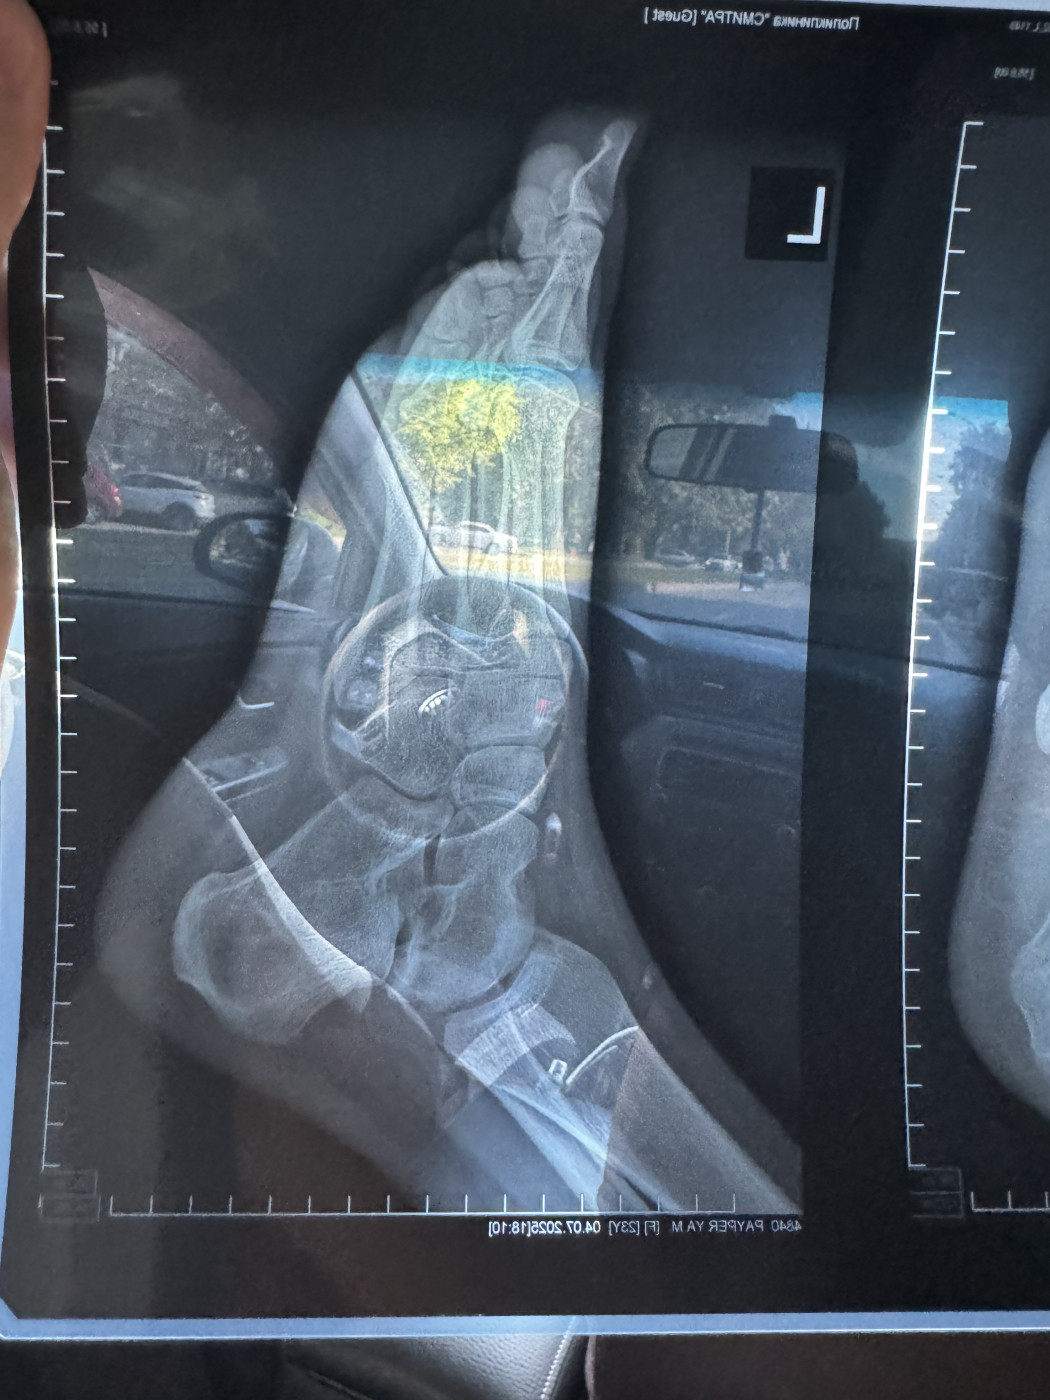

Жмет пластиковый ортезДобрый день! 3 ноября я сломала пятую плюсневую кость на левой ноге, перелом без смещения. Мне наложили гипс. 15 ноября после повторного рентгена (снимок от 15 ноября на фото) мне наложили пластиковый ортез ordect и сказали, что я могу ходить с опорой на пятку. Но этот ортез мне жмет, мизинец очень плотно прижат к другим пальцам. |